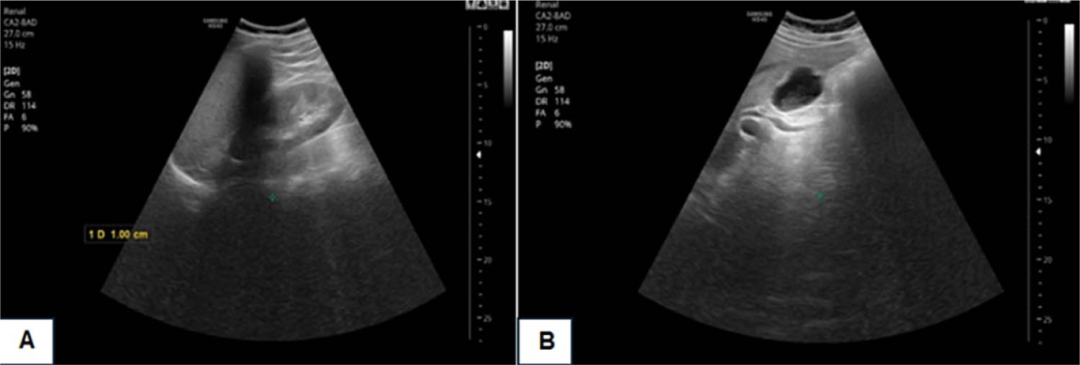

腹部超声检查显示:肝脏大小处于正常上限伴轻度脂肪浸润;胆囊大小正常,内见少量胆泥;胆总管(CBD)轻度扩张,直径8.5mm,CBD壁轻度增厚及回声增强(图 1)。

图1 腹部超声显示轻度肝脂肪浸润。胆囊大小正常,有0.8×0.4 cm少量胆泥(图B)